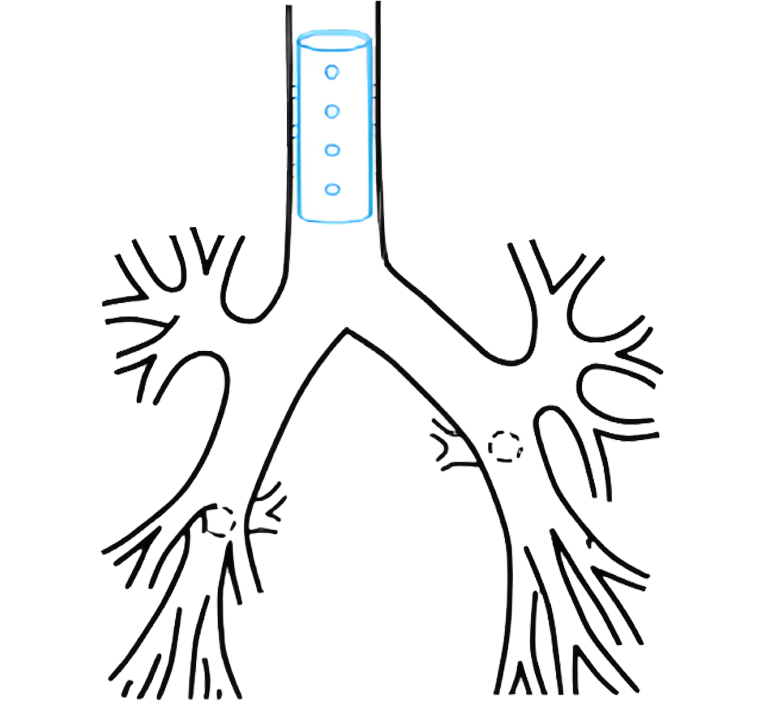

ستێنتکردن لە نەخۆشێکدا کە تەسکبوونەوەی لوولەی هەناسەی هەیە

وۆرک شۆپی پراکتیکی ستێنتکردنی سییەکان